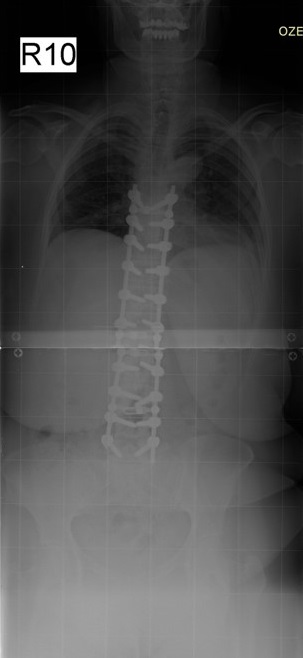

60 Yaşında Kadın Hasta

Ameliyat Sonrası